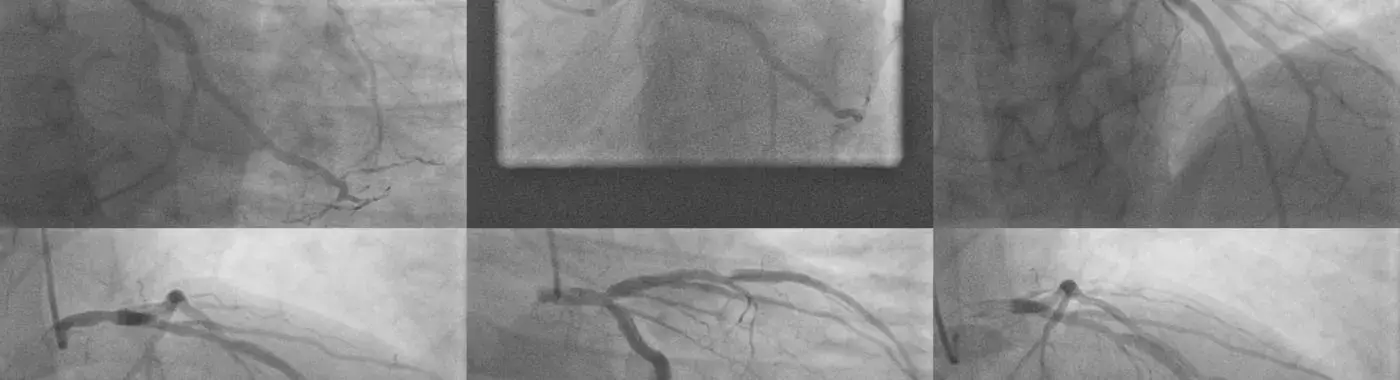

3. Coronary Angiography:

• Coronary angiography is the gold standard for diagnosing LMCA disease. It involves injecting a contrast dye into the coronary arteries and taking X-ray images to detect blockages or narrowing in the LMCA.